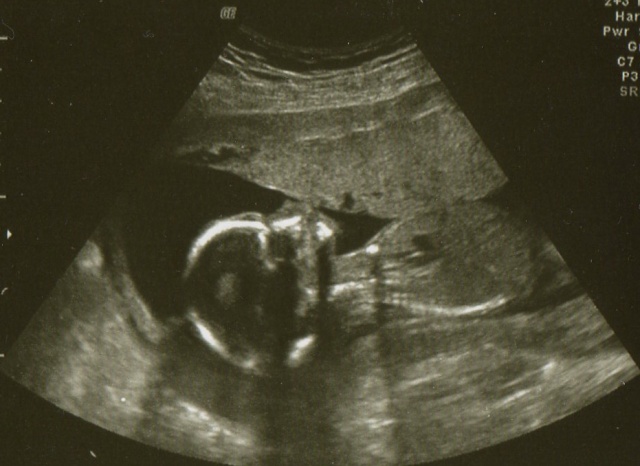

. Tak štědrej den je za námi a dopadl vpoho, dokonce naše babí ani nenadávala, že nevěděla o mimískovi manža jí udělal video s toho posledního UZ na genetice a dal k tomu hudbu prostě bájo, tak koukala jak puk jak se malej hýbe a tluče mu srdíčko to tam bylo i slyšet, tak byla ráda a prej konečně, že se ještě snad prcka dočká

. Tadyk vám dávám zatím jen obrázky mimíska ve 13+3tt a 17+4tt , stromeček a bříško vám sem dám, jak my to manža stáhne ze svého compu do mýho